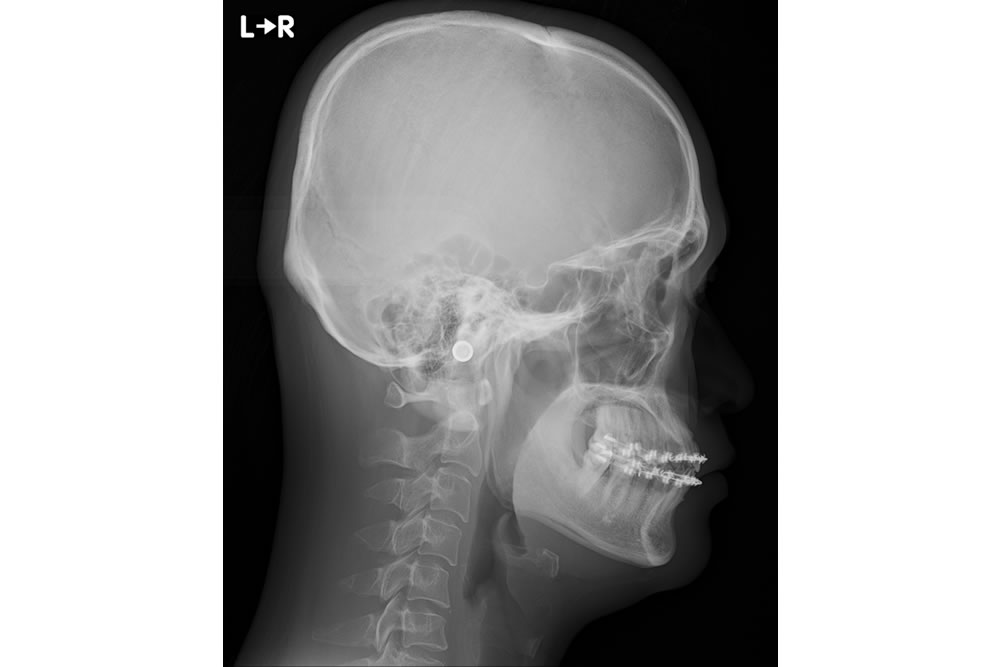

セファロレントゲン

セファロと呼ばれる、規格化されたレントゲンを大学病院で撮影してきてもらい、治療が可能か判断します。